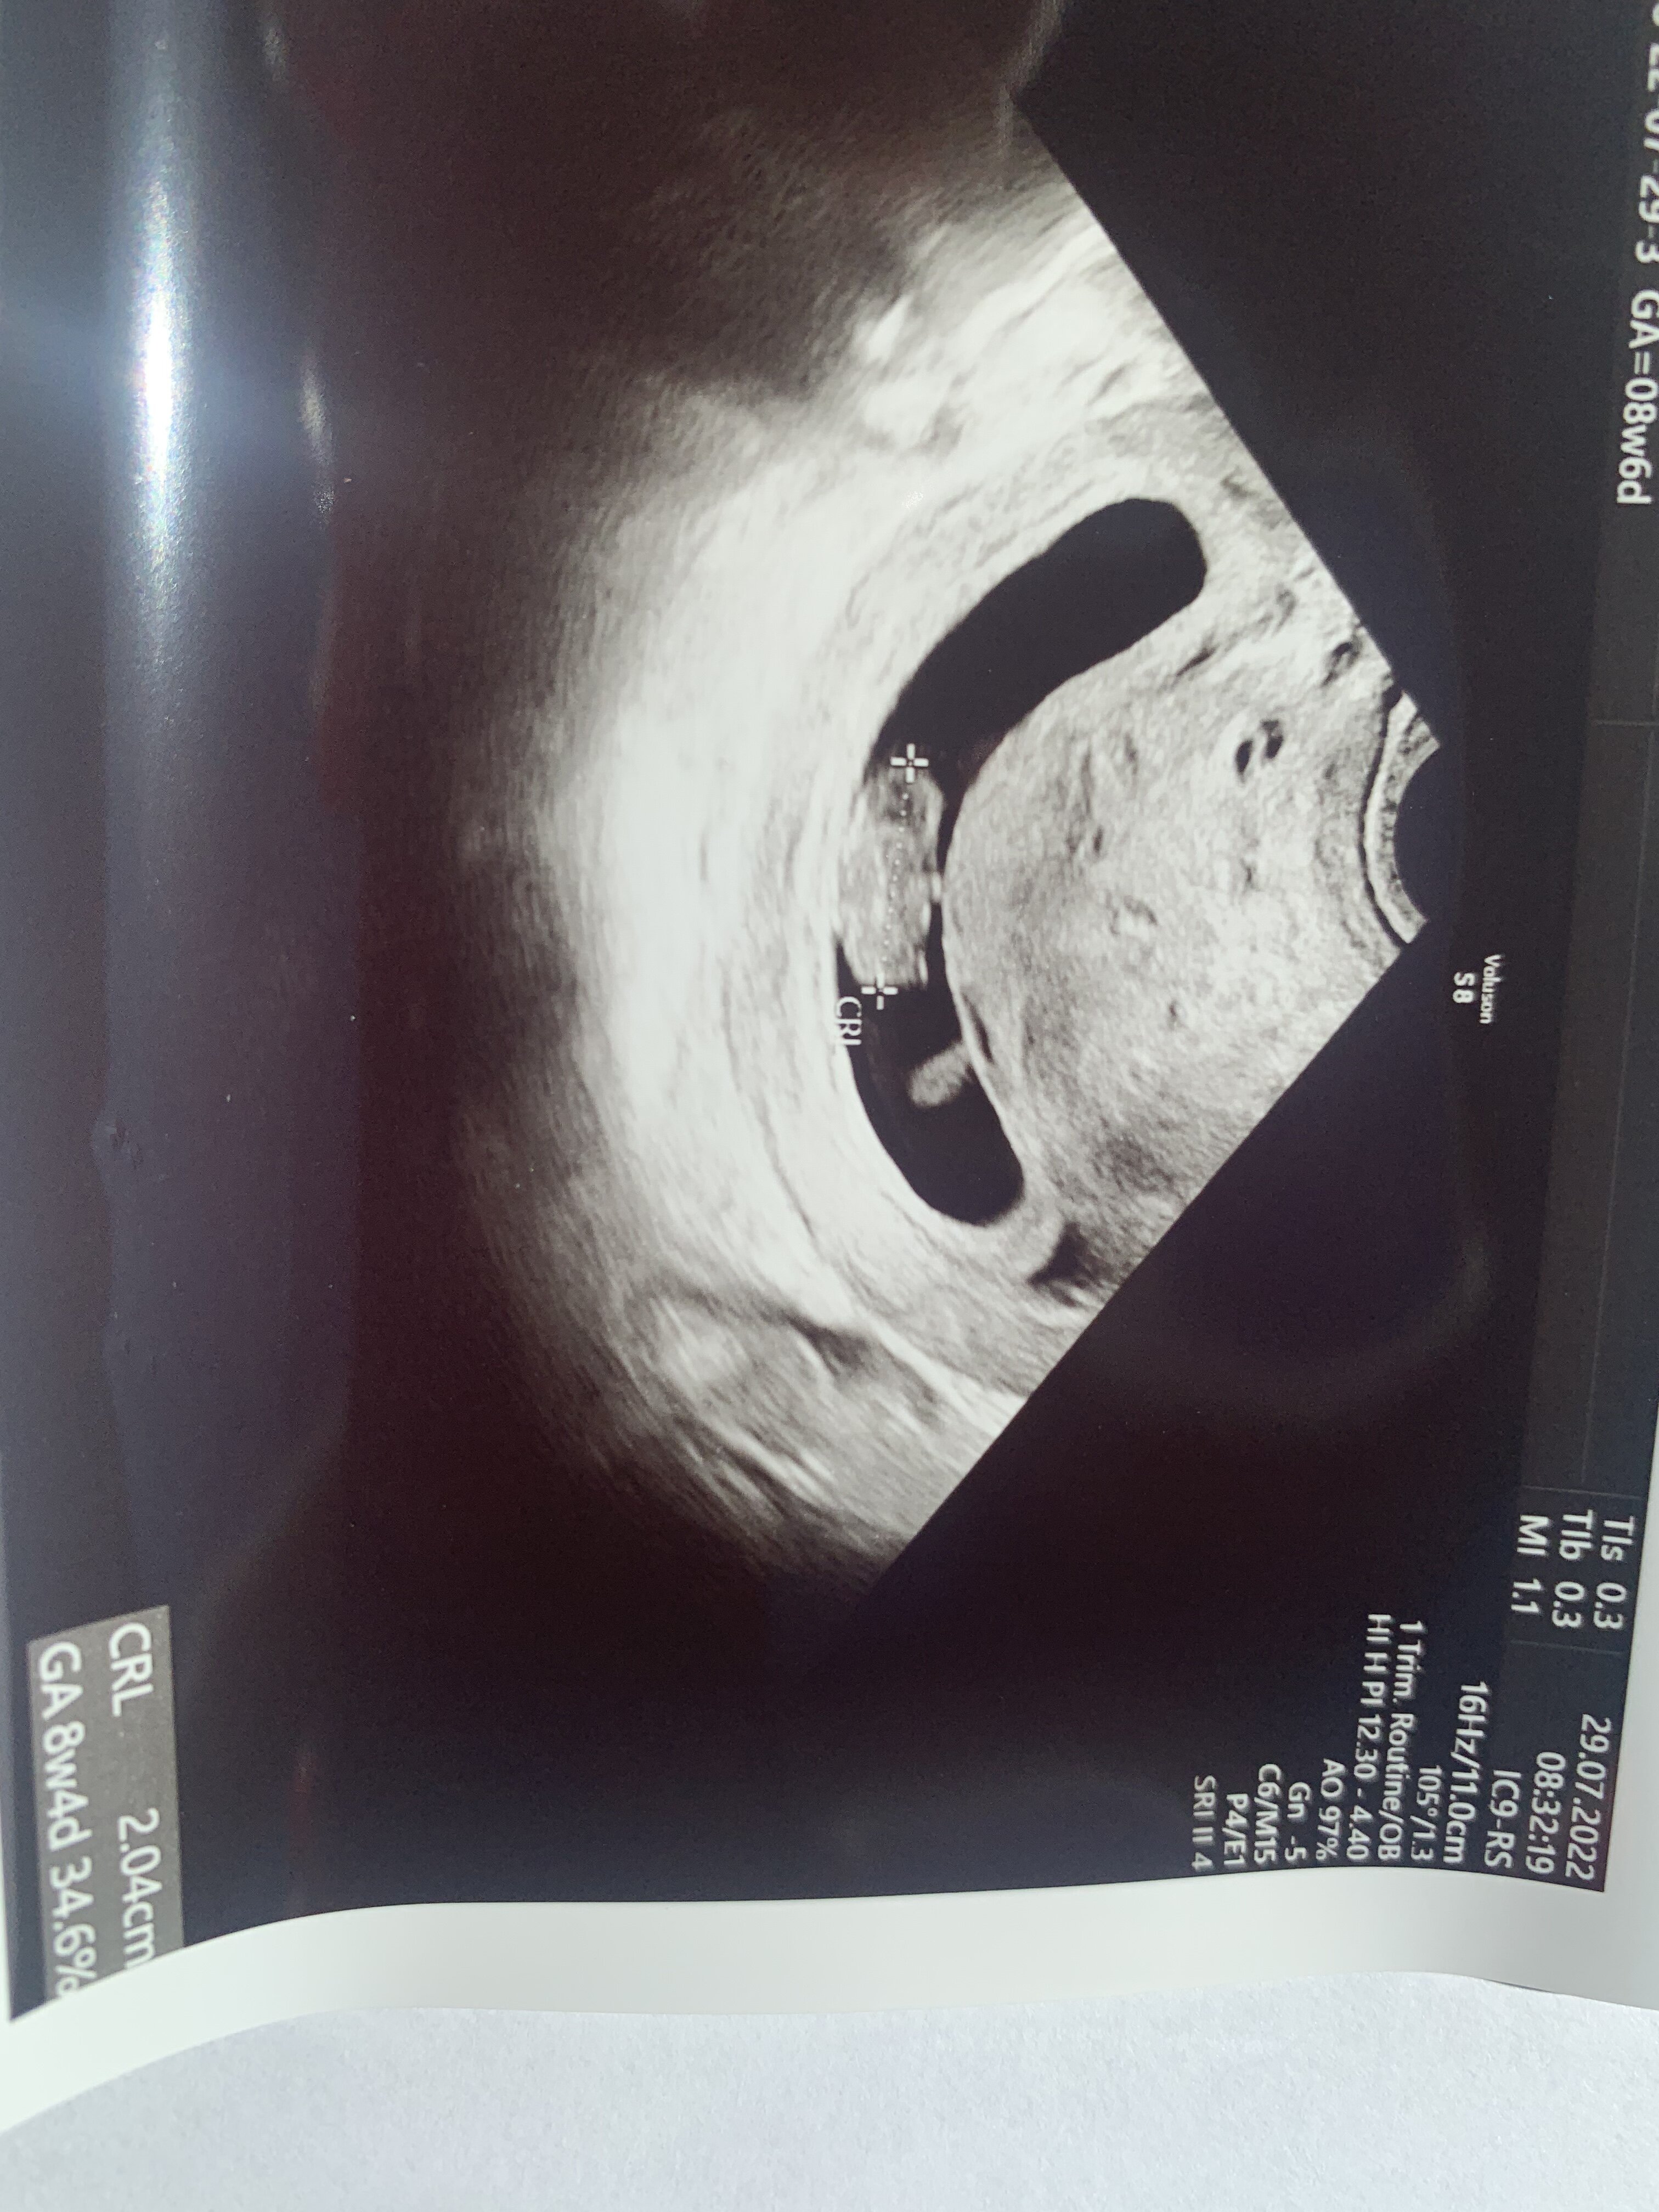

Tak trochę mało widać, ale załączamojej cudniepochwalisz się zdjęciem?

Super ! Który tydzień?![]()

U mnie odwrotnie starsza o 2-3dniTak trochę mało widać, ale załączam